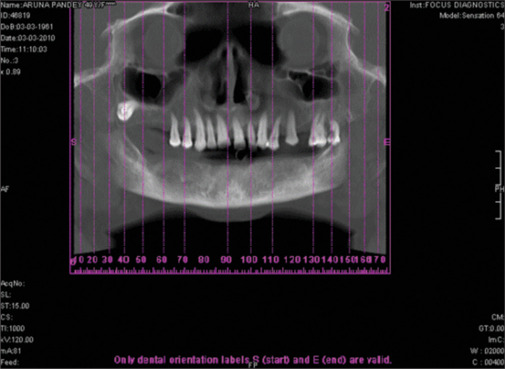

Purpose: The purpose of this study was to examine the relationship between the local bone density derived from a cone-beam computed tomography (CBCT) scan from different sites in the maxilla and mandible and the insertion torque values, for the success of oral implants.

Materials and methods: A total of 73 patients who reported to our unit, with missing teeth and a desire for replacement with dental implants, were included in this study. A total of 118 implants were placed from 2008 to 2011. The number of male and female patients included in the study was 43 and 30, respectively. The mean age of the patients was 43.2 years. NobelReplace Select Tapered Implant system was used for all patients.

Results: The mean bone density of all 118 implants was 620 ± 251 Hounsfield units (HU). The mean bone density and insertion torque values of the six failed implants were 459 ± 131 HU and 28 ± 5 Ncm, respectively. The mean bone density and insertion torque values of the 112 successful implants were 678 ± 217 HU and 36 ± 2 Ncm, respectively. A significant strong positive correlation was observed between bone density and torque at all sites.

Conclusion: CBCT is a useful tool to determine the bone density of the concerned areas before implant placement. The valuable information derived from the CBCT about bone quality may help clinicians to avoid the placement of implants into the very poorest qualities of bone, where failure is more likely.